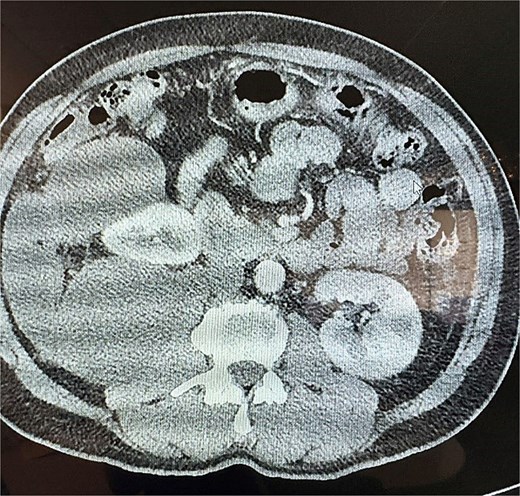

This is a 53-year-old male with no notable past medical history who presented with a 6-week history of persistent right-sided flank pain. Notably, the patient denied systemic symptoms such as weight loss, nausea, vomiting, or constipation and he denied any urinary symptoms, including dysuria or hematuria. Initial evaluation in the emergency department (ED) included a computed tomography (CT) scan of the abdomen and pelvis, which revealed a 23 cm cystic retroperitoneal mass displacing the right kidney as seen in Figs 1 and 2. The patient was discharged from the ED with a recommendation for follow-up with a surgical specialist.